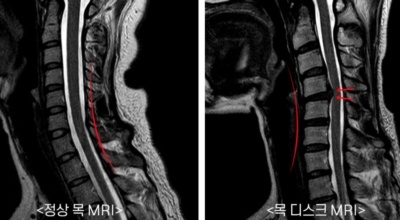

목디스크란

경추 사이의 추간판(디스크)이 탈출 또는 파열되어 경추신경이 자극이나 압박을 받아 통증이 생기는 증상을 말해요. 경추는 운동성이 큰 부위로 추간판이 압력을 받으면 튀어나와 척수나 신경을 압박하게 되는데요 목디스크는 퇴행성 변화 이후에 발생되기 때문에 많은 환자들이 만성적인 통증을 지니고 있는 경우가 많아요. 급성으로 생기는 경우는 교통사고, 추락, 스포츠 활동에 의한 목 부상으로 나타나기도 해요. 20대부터 가벼운 초기 증상으로 시작하여 옳지 않은 습관으로 악화되거나 호전되기를 반복해요. 나이가 들면 퇴행성 변화로 40~50대에 가장 많은 환자 수를 보인다고 합니다

목디스크가 생기는 가장 큰 원인은 거북목과 일자목입니다. 신체의 가장 무거운 부분을 지지하는 경추는 옆에서 보았을 때 자연스러운 C자 모양을 보존시켜야 해요. 그러나 이 자세를 올바르게 유지하지 않고 머리를 숙이면 목의 무게는 머리 무게의 5배가 될 수 있어요. 이 경우에 목디스크가 발생해요. 거북목, 일자목 등 구부정한 자세를 방치하게 되면 어깨와 목 근육에 계속하여 압박이나 무리를 줌으로 인해 조기 치료가 중요해요. 목디스크를 방치하게 된다면 어깨 근육, 팔목, 손가락의 저림증상부터 마비증상까지 나타날 수 있답니다.